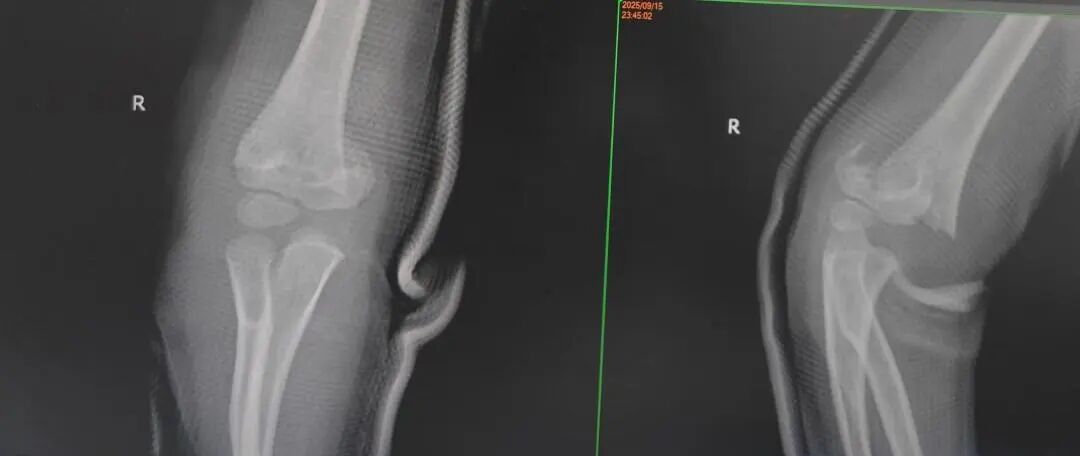

4岁的小罗:9月15日,在家追跑玩耍时撞到桌角,右侧肱骨髁上骨折;

7岁的小周:9月15日,在家爬沙发时摔落,左肱骨外髁骨折;

10岁的小唐:9月18日,在学校操场奔跑时摔倒,左肱骨髁上骨折……

同样“抢时间”的还有小罗和小周的治疗:4岁小罗9月15日深夜入院,10小时后顺利手术;7岁小周同一晚受伤,也在10小时内完成肱骨髁上骨折闭合复位经皮固定术。6岁小郑更是创下“4小时极速手术”纪录——早晨7点40分受伤,8点多入院,11点多手术结束,当天下午就能躺上网课。